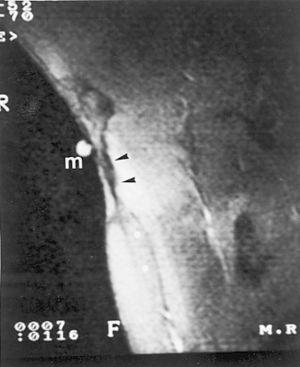

Una nueva resonancia magnética a los 12 meses detecta un engrosamiento de la fascia del LD con retracción muscular del mismo. Se añaden cortes axiales y coronales en abducción y rotación externa con la finalidad de poner en tensión al LD. La reparación fibrosa muestra mayor retracción de las fibras más distales las más laterales del músculo (fig. 6). Esta retracción produce el efecto de hachazo y descubre el tendón desnudo del TM. En la zona miotendinosa axilar se observa el proceso cicatricial sin signos de afectación inflamatoria crónica.

Figura 6 Control con resonancia magnética a los 12 meses. Imagen frontal con el brazo en abducción y rotación externa, con marcador cutáneo (m). Se identifica una clara secuela cicatricial (flechas negras) sin signos de edema perimuscular y clara retracción en el Latissimus dorsi (asteriscos).